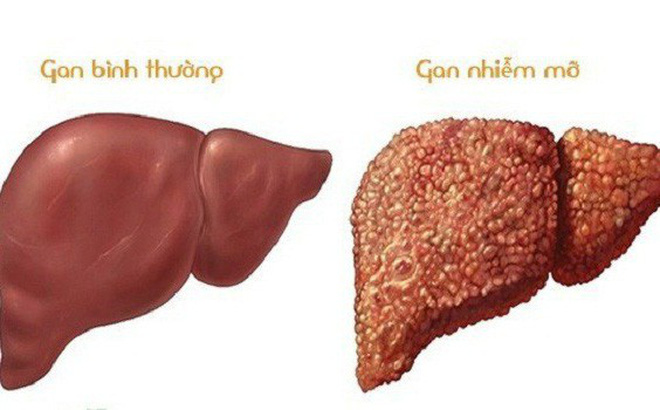

Đồ chiên rán là món ăn hấp dẫn và quen thuộc trong khẩu phần của nhiều người. Tuy nhiên, việc tiêu thụ quá nhiều thực phẩm nhiều dầu mỡ có thể gây ra những ảnh hưởng nhất định đến sức khỏe, đặc biệt là đối với gan – cơ quan đóng vai trò quan trọng trong quá trình chuyển hóa và giải độc của cơ thể.